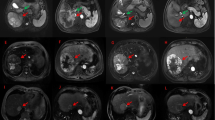

Several studies have reported improved responses for MVI compared to intrahepatic lesions in patients receiving systematic therapies, including tyrosine kinase inhibitors or immunotherapy45,46. Thus, we further defined the response of MVI based on the downstaging (PR) or upstaging (PD) of MVI extent (Supplementary Table 8)16. The results demonstrated no significant correlation of responses between MVI and the primary tumors (p = 0.402), and the ORR for MVI was comparable with that for primary tumors (33.3% versus 30.0%). However, the DCR for MVI was higher than that for intrahepatic tumors (93.3% versus 36.6%), which may be explained by the radiosensitivity of MVI cells to irradiation20, or the higher intrahepatic tumor burden and the unfavorable immunosuppressive microenvironment of the liver47.